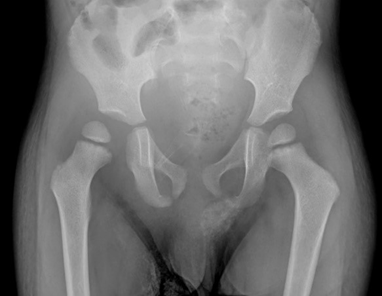

En su cuarto día de postoperatorio el paciente vuelve a cursar con distensión abdominal y dolor intenso irradiado a cadera y miembro inferior derecho con edema, hipertermia localizada y con limitación para la extensión, rotación y abducción; por lo cual se realiza una ecografía articular de cadera derecha y una ecografía abdominal sin reporte de hallazgos patológicos. Adicionalmente se realiza una radiografía de cadera donde se observa subluxación coxofemoral derecha (fig.1).

Figura 1. Radiografía AP de pelvis que demuestra aumento de volumen de partes blandas y subluxación coxofemoral derecha